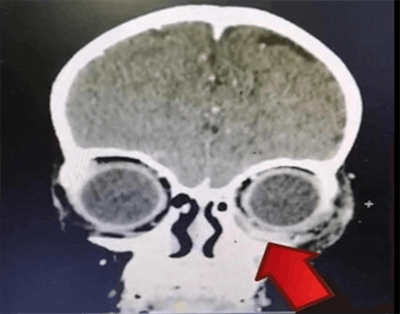

Contrast-enhanced CT of the orbit, paranasal area, and brain showed a left periosteal abscess collection that extended into the left orbit and maxillary and ethmoidal sinuses. A dental exam and tooth extraction were completed while the girl was under general anesthesia, and the dentist discovered a left upper gum abscess. A culture was taken, and no organism was isolated.